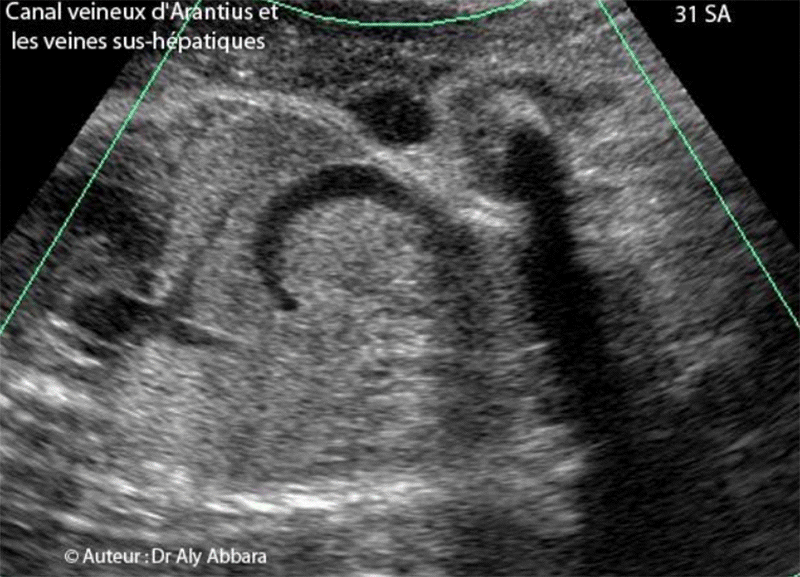

Canal veineux et veines sus-hépatiques - Anatomie échographique

Image échographique montrant le canal veineux d'Arantius reliant la veine ombilicale à la partie terminale de la veine cave inférieure (pratiquement, directement à l'oreillette droite) puis deux des trois veines hépatiques (sus-hépatiques). L'image montre aussi la nécessité d'utiliser le Doppler couleur (ici, c'est le Dynamic-flow) pour mettre en évidence le canal veineux, étant invisible autrement.

Le spectre du Doppler de ses veines est différent, ce qui permet mieux les identifier.